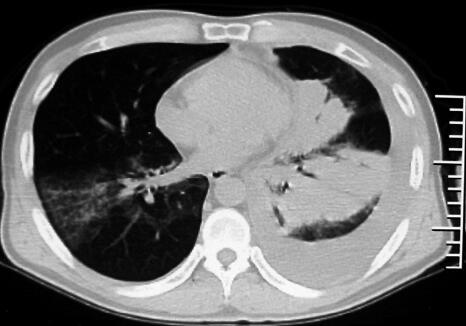

10.胸部影像学:双肺多发斑片影(图1)。

图1

重要的检查结果有四项:①血常规:白细胞总数、中性粒细胞比率均略增高;②胸部影像学:胸部CT示双肺以肺门为中心对称的斑片影;③肺功能:FVC、FEV1均减低,FEV1/FVC%正常,DLCO:74%预计值。④血气分析:PaO2 62mmHg,PaCO2 34mmHg,P(A-a)O2 41mmHg。

结合患者的病史和体格检查结果,目前仍考虑肺部感染性疾病——社区获得性肺炎(community acquired pneumonia,CAP)的诊断,但目前病原学尚不明确。患者发病以来曾静脉滴注过四代头孢(头孢吡肟)7天,仍有咳嗽、气短,体温一度降至正常,但后来再次出现发热,考虑抗生素可能未完全覆盖病原体。双肺多发斑片影累及多肺叶并影响到气体交换,因此患者仍有气短。进一步的处理应是立即选择合适的抗感染药物进行治疗,其目的有二:①治疗感染;②通过治疗明确或修正诊断。